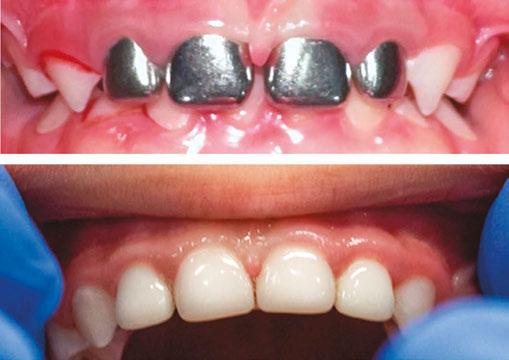

One family’s experience highlights the transformative impact of Dr. Villalta’s approach. Xio’s mom stumbled upon Dr. Villalta’s TikTok page in a moment of desperation when searching for a way to restore her child’s smile and confidence after she had stainless steel crowns placed on her anterior teeth.

Upon Xio’s first visit to The Baby Teeth Studio, Dr. Villalta and her team immediately recognized the emotional toll the previous treatment had taken on the young girl. “Xio was

apprehensive, extremely nervous, anxious, and withdrawn,” Dr. Villalta remembers. “It was heartbreaking to see how much her selfesteem had been affected. Her parents mentioned Xio stopped smiling like she used to prior to the placement of silver crowns on her front teeth.”

We replaced SSC with NuSmile Zirconia Anterior Crowns. The transformation was incredible with her appearance, comfort, and confidence.”

Dr. Villalta devised a treatment plan that not only addressed Xio’s dental needs, but restored her confidence. “We replaced Xio’s stainless steel crowns with NuSmile ZR Anterior Zirconia Crowns,” she explains. “The transformation was incredible with her appearance, comfort, and confidence.” Xio’s mom also noticed an immediate change in her daughter. “She couldn’t stop smiling and showing off her new teeth,” she reports. She was also struck by the contrast between their initial traumatic experience at the prior dental practice, which she described as “literally like an assembly line,” and the personal, compassionate treatment they received at The Baby Teeth Studio.

Xio pre-op and 3-month post-op with NuSmile ZR Crowns